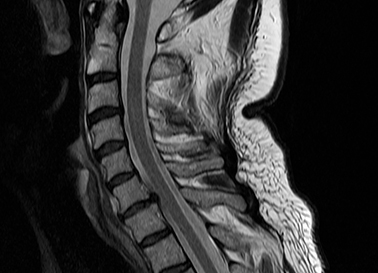

Magnetresonanztomographie

Hier finden Sie wichtige Hinweise zu dieser Untersuchungsmethode (Kernspintomographie, MRT).